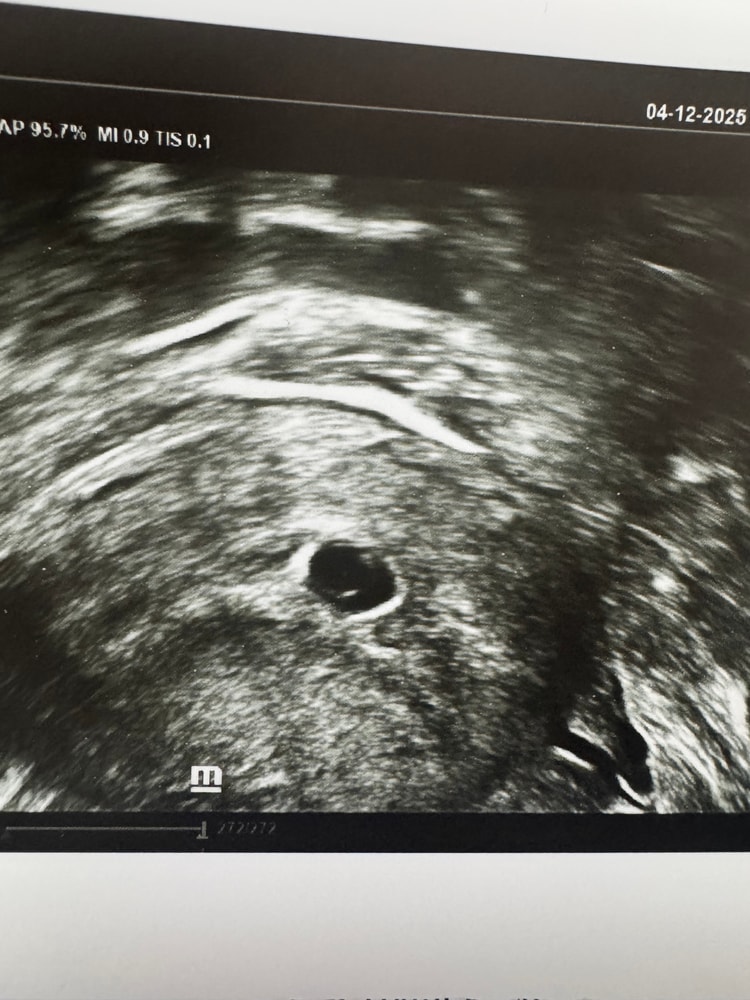

Наталия, вот мой пупсик с последнего узи, сверху эмбрион, снизу жм Изображение